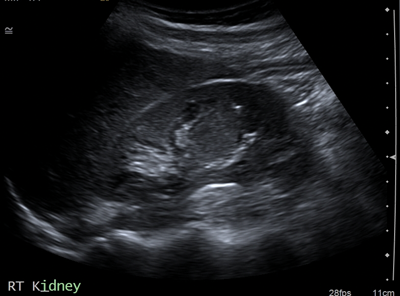

Horseshoe kidney

A horseshoe kidney (Figure 1) is a congenital anomaly in which kidneys are fused by the isthmus at the lower poles. In 90% of cases this is a midline, or symmetrical fusion, but lateral fusion is also a variant. The axis of each renal pelvis remains vertical or in the obliquely lateral plane, and the calyces point posteriorly. The horseshoe kidney lies ectopically with the isthmus located adjacent to the L3 to L4 level. This is due to the inferior mesenteric artery preventing further ascent as it crosses the isthmus. Approximately one third of horseshoe kidneys have a single renal artery to each renal pelvis, whereas the remainder have a variable blood supply [1].

The incidence is 1 in 400 and it is the commonest renal fusion anomaly. There is a male predominance with male to female ratio 2:1. It is often asymptomatic, but patients may present with vague abdominal pain, radiating to the back, ureteral obstruction, or palpable midline abdominal mass. Approximately 50% of horseshoe kidneys have associated vesicoureteral reflux and 30% of patients develop urinary tract infections [1]. Horseshoe kidneys have increased risk of traumatic injury, due to the isthmus lying anteriorly without the protection of the ribs, and it can be split by high impact blunt abdominal trauma [2].

On the plain abdomen film the lower poles of the kidneys are seen medial to the upper poles, in contrast with normal renal anatomy where lower poles are lateral. Ultrasound may reveal the isthmus lying anterior to the spine and contiguous with the lower poles of both kidneys. However due to the positioning of bowel gas centrally, the isthmus may not be clearly viewed and appearances may be of a curved configuration to the kidneys with poorly defined lower poles. In the longitudinal plane the kidneys may appear as an inverted triangular or pyriform shape [3,4]. Contrast enhanced CT will provide the clearest imaging, and helps to define the structural abnormalities of the horseshoe kidney. On CT the following questions can be answered: the degree and site of the fusion, degree of renal malrotation, any associated collecting system abnormalities, and any renal parenchymal changes. CT enables differentiation between normal and fibrous parenchyma within the isthmus, which is almost always functioning tissue.